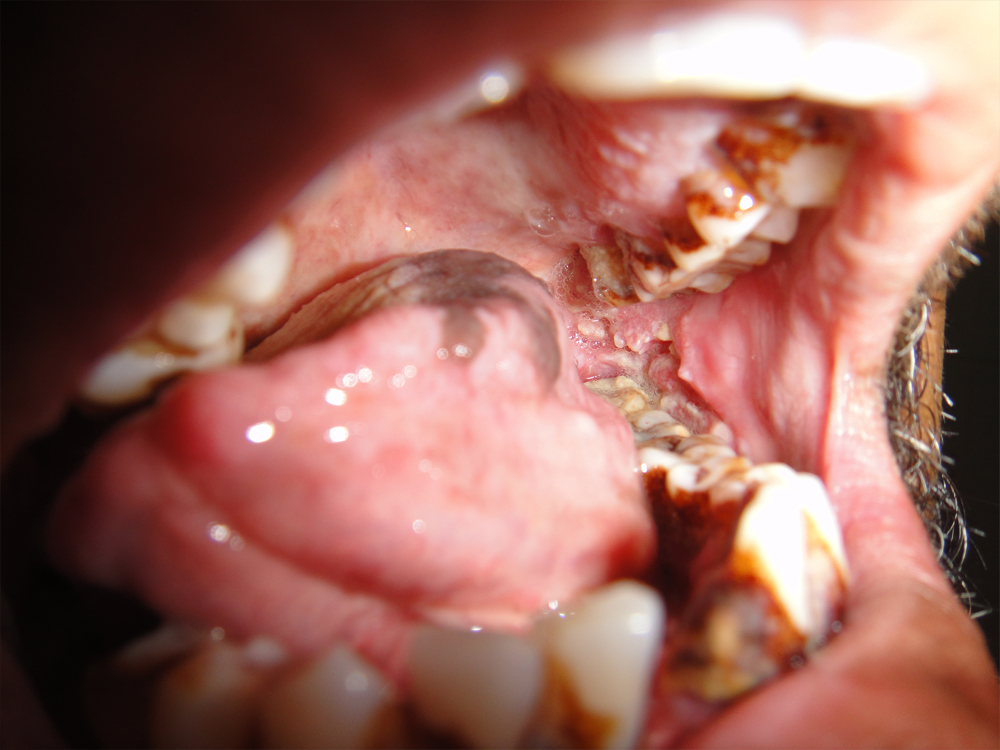

75 yrs old patient having right upper alveolus carcinoma.patient was operated for right buccal mucosa carcinoma in 2009.pet ct shows localised disease with minimal uptake in left neck node.Right subtotal maxillectomy done with Right PM flape.